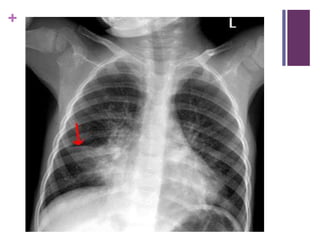

6 yo SOB/Chest pain/Dysphagia

– r/o Popcorn L main bronchus